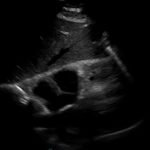

Bedside echocardiogram was performed, which revealed a free-floating thrombus in the right atrium on the sub-xiphoid view as seen in the video. The right atrium is denoted by the blue circle, in which a hyperechoic mobile mass can be seen. This finding was confirmed by an official echocardiogram which shows the thrombus in the right atrium extending through the tricuspid valve, as shown in the second image denoted by the red arrow. Significant right heart strain was also found, with severe pulmonary hypertension and intraventricular septal flattening.